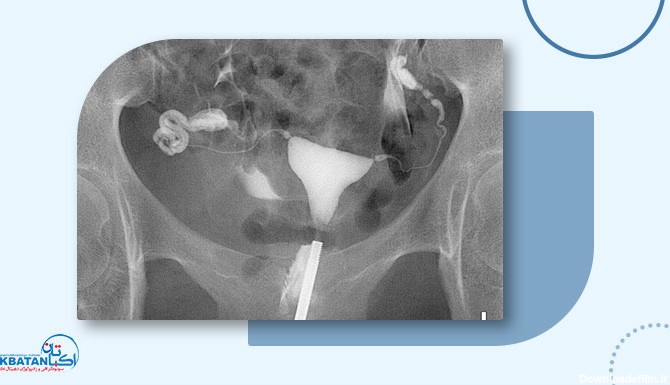

عکس رنگی رحم چیست؟ یک آزمایش اشعه ایکس که برای بررسی رحم و لوله های فالوپ و ناحیه اطراف آنها نگاه می کند و برای بررسی مشکلات ناباروری ممکن است انجام شود.

عکس رنگی رحم (هیستروسالپنگوگرافی ) به ۲ صورت با بیهوشی و بدون بیهوشی انجام می شود. برای تشخیص اختلال رحم و سقط مکرر و ناباروری . جزییات کامل را بخوانید

عکس رحم یا هیستروسالپنگوگرافی (Hysterosalpingography) چیست و بهترین زمان انجام عکس رنگی رحم و مزایا، عوارض، خطرات و کاربرد انجام آن چیست و چگونه انجام میشود